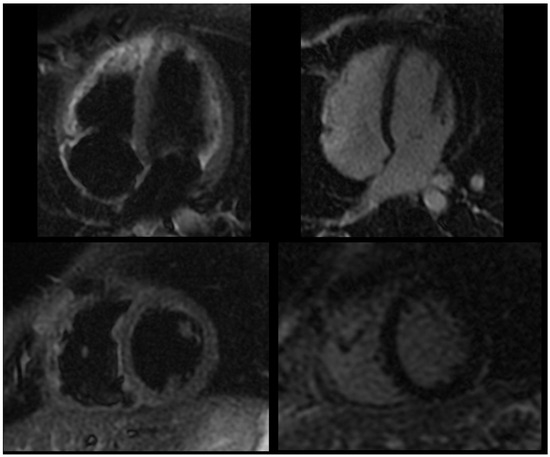

2.2. Current Assessment and Differential Diagnosis